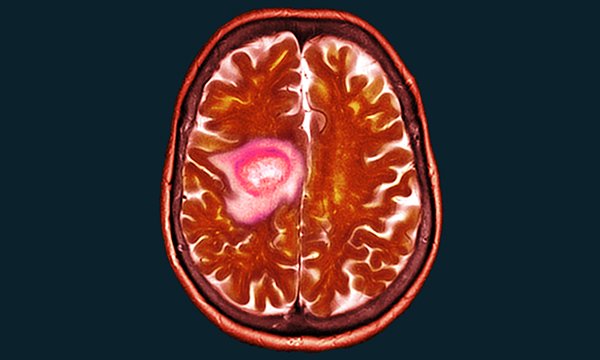

People are surviving cancer for longer, but there may be long-term effects nurses should be